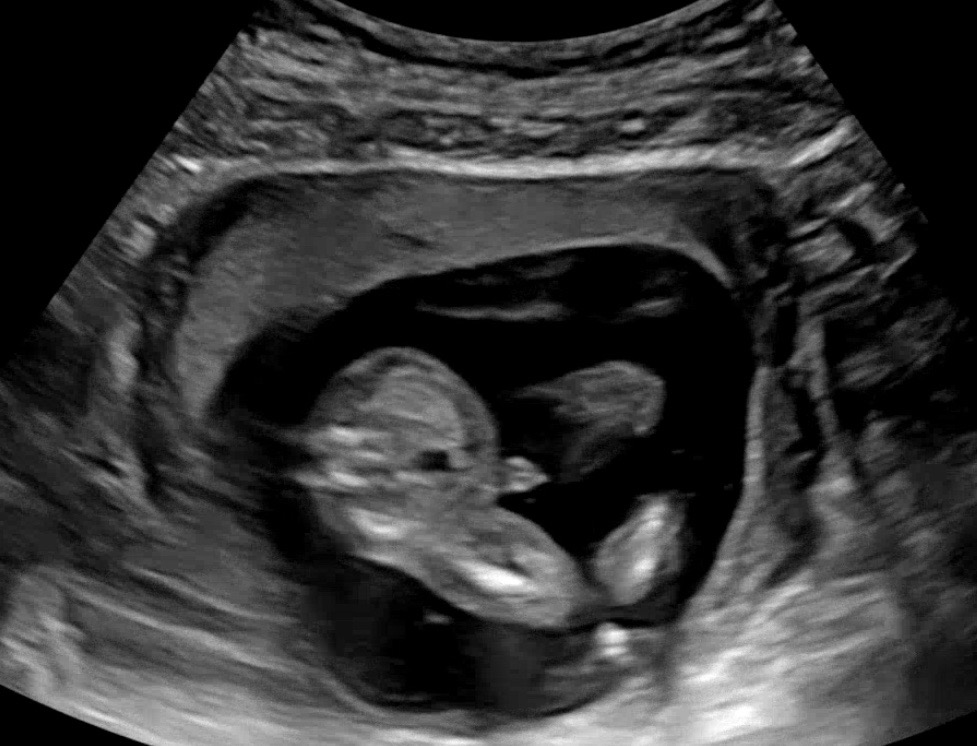

16주 초음파 보고왔는데 반전은 없는거겠죠..?